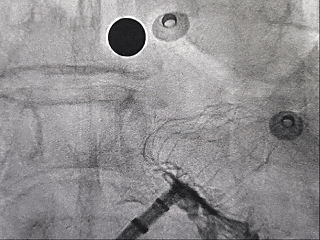

DSA造影复测缺损

右肩位:RAO 30° +CRAN 20°

肝位:RAO 30° +CAU 20°

术中肝位测量:

心耳开口直径:24.9mm

心耳深度:26.9mm